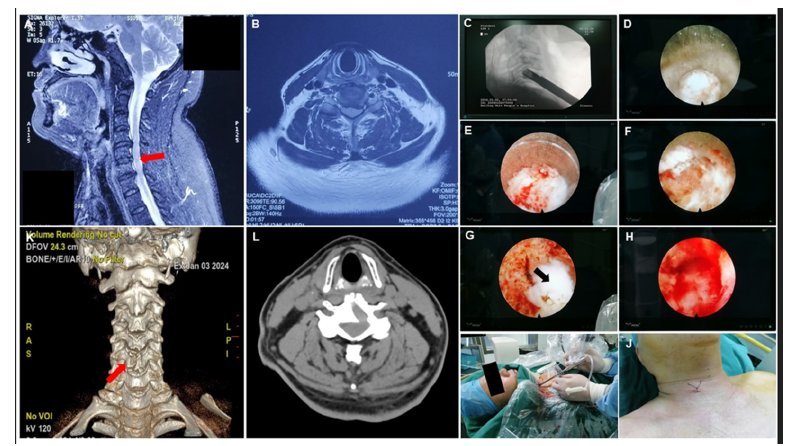

Then, the cryogenic plasma knife (DZX-G3040-A340, Shaanxi, China) was carried out to reveal the surface of vertebral body and disc by clearing surrounding tissue, especially the prevertebral fascia. Controlling bleeding promptly was needed to ensure a clear surgical field during the exposure of the vertebra. Moreover, the position of the trephine was observed and adjusted to bring it close to the center of the vertebral body and avoid pedicle damage, under C-arm lateral fluoroscopy. The selection of the endoscope and trephine was as follows: If the patient’s intervertebral disc width was greater than 18mm, a 6.9mm endoscope and an 8.0mm trephine were chosen; If the patient’s intervertebral disc width was less than 18mm, a 5.3mm endoscope and a 6.4mm trephine were selected. The trephine then rotated and cut from the anterior inferior of the inferior vertebra direction to the posterior superior direction along the vertebral body. For instance, if the compression site of CSM patient is between C5 and C6, the trephine is used to rotate from the anteroinferior aspect of the C6 vertebra in a posterior-superior direction until reaching the posterior longitudinal ligament. This was the so-called trans vertebral approach. The aforementioned rotated cutting process carries certain risks of internal fracture collapse; therefore, it is necessary to proceed under continuous guidance from the C-arm fluoroscopy. The herniated intervertebral disc material and the osteophytes were removed successfully to adequately decompress the spinal cord, allowing for good dural pulsation to be observed. During decompression, a continuous flow of saline with a degree of pressure should be maintained to ensure a relatively bloodless operative field. Finally, the instruments including the endoscope, trephine, and working cannula were removed and the incision was closed without drain (Figure 1).

Fgure 1:The surgical procedure. Note: A: The MRI of the patient before surgery. The compression site is marked with red arrow at the junction of the C5 and C6 spinal cord segments; B: patient pre-operative MRI cross-section; C: the front-end of trephine touched the anterior inferior of the vertebra under C-arm lateral fluoroscopy; D, the paravertebral fascia is exposed; E, the process of rotating and cutting using trephine; F, the process of rotating and cutting using trephine; G, the nucleus pulposus is exposed (black arrow); H, the dural sac is exposed, and the pulsation of dural sac can be observed under direct endoscopic visualization. I, surgery in progress; J, the skin was closed by surgical stitching; K, CT guidance and 3D reconstruction after surgery; L, patient post-operative CT cross-section.